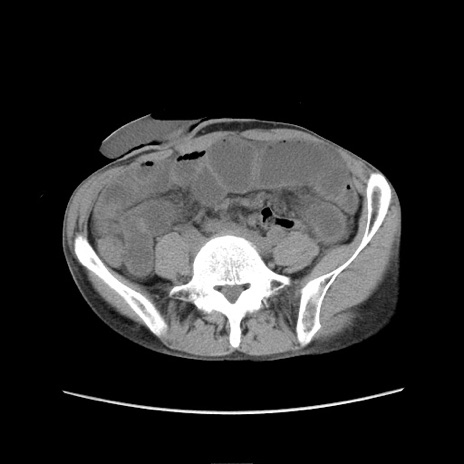

症例11(横断像)

【症例】 60歳代男性

【主訴】 下腹部痛

【現病歴】 本日夜中より下腹部痛の症状認め、受診。

【既往歴】 膀胱癌(膀胱全摘+尿管皮膚瘻術) 、胃癌術後

【身体所見】 BT 35.3℃、PR 58/min、BP 136/98mHg、腹部平坦、軟、腸蠕動音±、ストマ留置あり、左上腹部~正中部に圧痛あり、反跳痛なし。

【データ】WBC 5100、CRP0.01